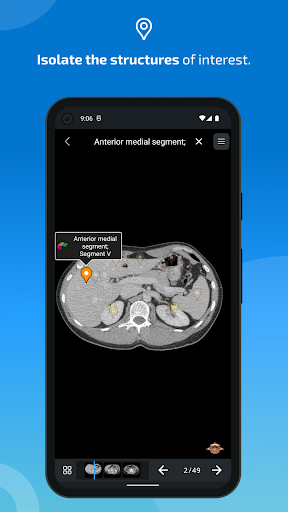

- Toque las etiquetas para mostrar las estructuras anatómicas

-El modo pines tiene un nuevo comportamiento que le permite seguir una estructura anatómica mucho más fácilmente

-Dentro de la vista de detalles de una estructura anatómica , un alfiler ahora señala la estructura relacionada en todas las imágenes presentes